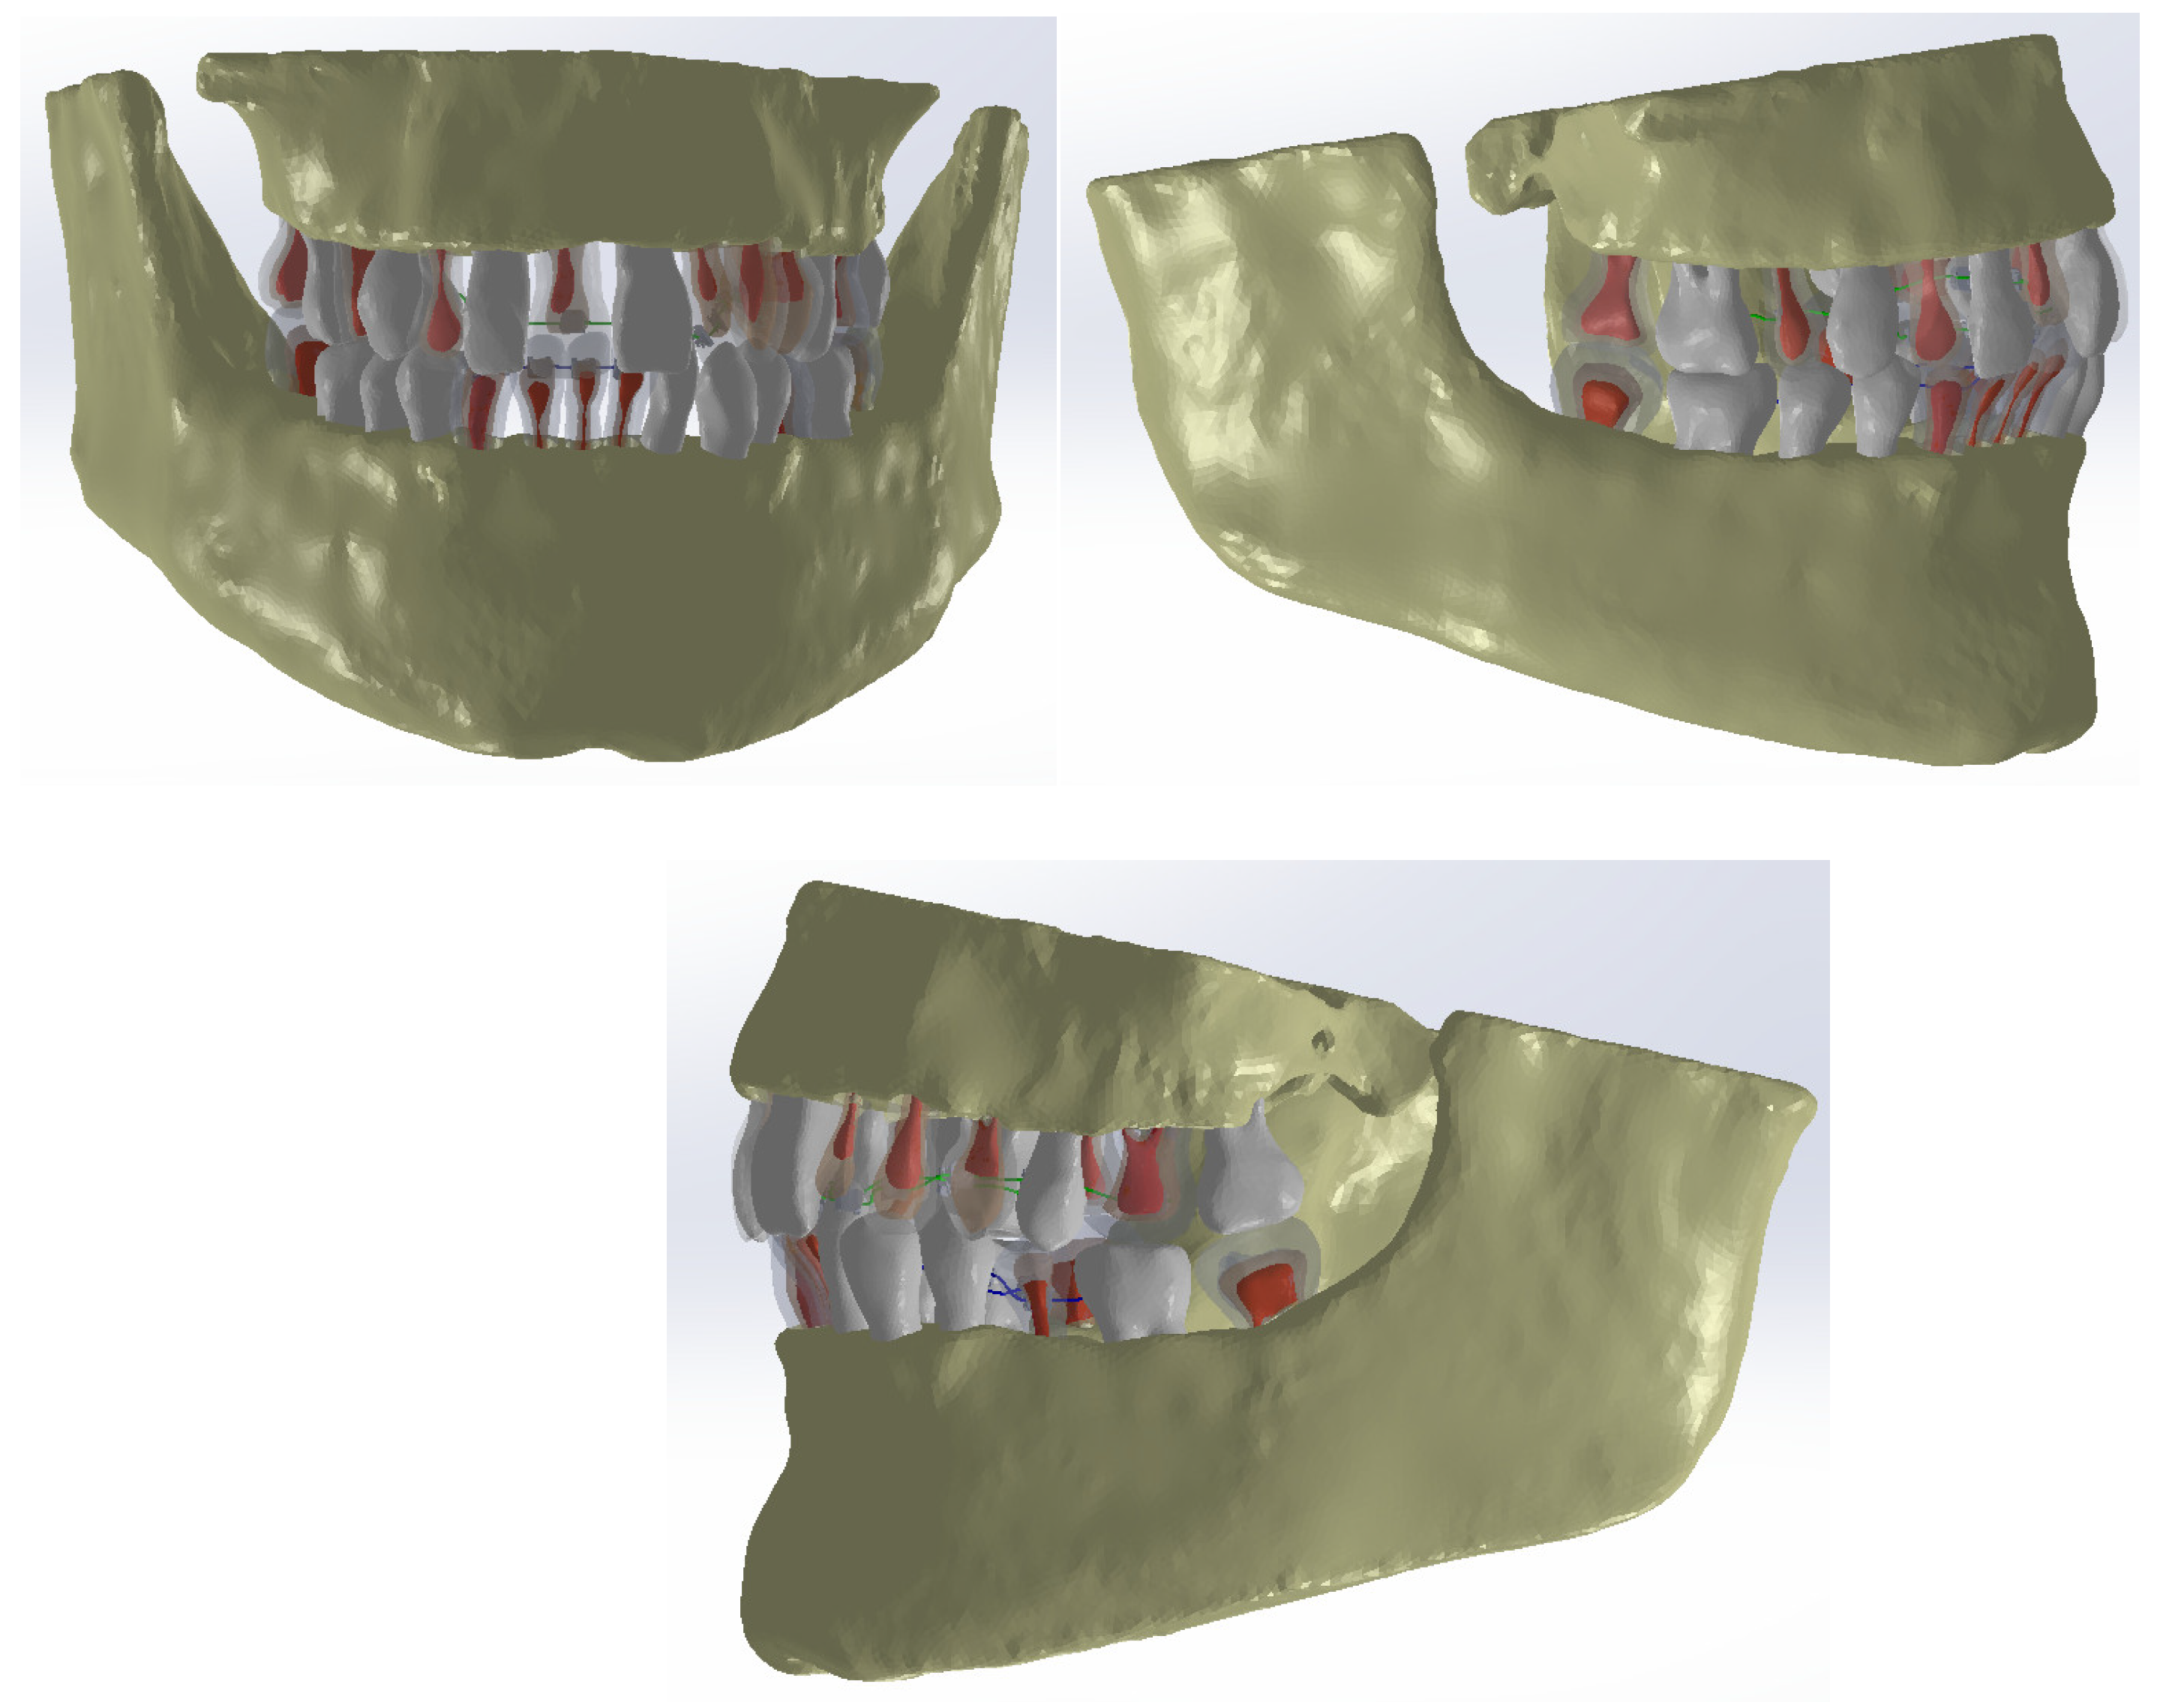

- Popa, D.; Duță, A.; Pitru, A.; Tutunea, D.; Gherghina, G. About the Simulation Environment for Dental Implant Studies. Sci. Bull. Politeh. Univ. Timis. Hidroteh. Ser. 2014, 58, 137–141. [Google Scholar]

- Vătu, M.; Crăițoiu, M.M.; Vintilă, D.; Mercuț, V.; Popescu, M.S.; Scierciu, M.; Popa, D.L. Determination of resistance forces from mandibular movements through dynamic simulation using kinematic analysis and finite elements method. Rom. J. Oral Rehabil. 2018, 10, 20–28. [Google Scholar]

- Vătu, M.; Vintilă, D.; Popa, D.L. 3D Skull Virtual Model Based on CT or MRI Images Used for Dentistry Simulations. Appl. Mech. Mater. 2018, 880, 101–110. [Google Scholar] [CrossRef]

- Petrescu, S.M.S.; Tuculină, M.J.; Popa, D.L.; Duță, A.; Sălan, A.I.; Voinea Georgescu, R.; Diaconu, O.A.; Turcu, A.A.; Mocanu, H.; Nicola, A.G.; et al. Modelling and Simulating an Orthodontic System Using Virtual Methods. Diagnostics 2022, 12, 1296. [Google Scholar] [CrossRef] [PubMed]